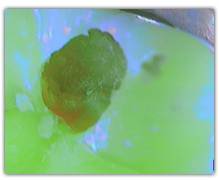

Does SOPROLIFE generates « False alerts »?

When SOPROLIFE generates a red fluorescence in a fissure, it is either due to a caries or to organic deposits. In this case a cleaning (pounce bag, air abrasion linked to Na bicarbonate ) is advised only in the suspicious fissure in order to avoid a falser alert.

The spectrum of the signal of fluorescence (let’s call it "its color") is rather in the green when the dentine is healthy and red/dark when the dentine is infected.

If the treatment aid mode is used for diagnosis purpose, we will obtain on screen an amplification of the red and thus get many « false alerts » due to organic deposits in the mouth of the patient. All these organic deposits generate un very light signal of red fluorescence. If the Mode II was used for the detection a caries, a complete cleaning of the mouth would be necessary to avoid these “false alerts”. The diagnosis aid mode, far less sensitive to all these organic deposits , allows to avoid these « false alerts ».